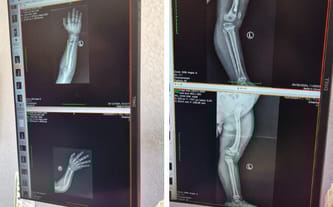

Wróciliśmy właśnie z Warszawy, gdzie przeprowadzono szczegółowe badania, w tym zdjęcia RTG. Niestety okazało się, że prawa ręka Huberta jest wygięta bardziej, niż początkowo zakładano. W związku z tym lekarze zdecydowali, że planowane jednorazowo operacje trzeba będzie podzielić na etapy. Jest to konieczne, aby Hubert miał sprawne i silne ręce, które pozwolą mu chodzić o kulach po operacjach nóg.

W pierwszym etapie, zaplanowanym na styczeń-luty, lekarze zamierzają wyprostować wygięcie w prawej ręce oraz umieścić gwóźdź stabilizujący, aby zapobiec ponownemu zniekształceniu. Niestety, będzie to już trzecia operacja na tej ręce. Z kolei lewa ręka wymaga wyjęcia płytek i śrub, ale jej stan jest zdecydowanie lepszy.

Pomimo trzech przeprowadzonych operacji, stan prawej ręki synka nadal budzi poważne obawy. Kości rosną nierówno, co powoduje ich wygięcie! Jeżeli choroba będzie postępować, konieczna będzie kolejna operacja ręki, aby skorygować deformacje i zapobiec dalszym komplikacjom...

Najbliższe zabiegi mają odbyć się w grudniu. Plan leczenia obejmuje uruchomienie gwoździa w kości udowej, co pozwoli na jej wydłużenie o 5 cm. Dodatkowo, podczas tej samej operacji, planowane jest wstawienie gwoździa do kości piszczelowej. Dzięki temu możliwe będzie nie tylko wyprostowanie, ale również wydłużenie kości piszczelowej, która rośnie krzywo i powoduje wygięcia... Od kilku lat stanowi to duży problem. Przeprowadzenie tych zabiegów podczas jednej operacji jest konieczne, aby zminimalizować ból i dyskomfort Huberta.